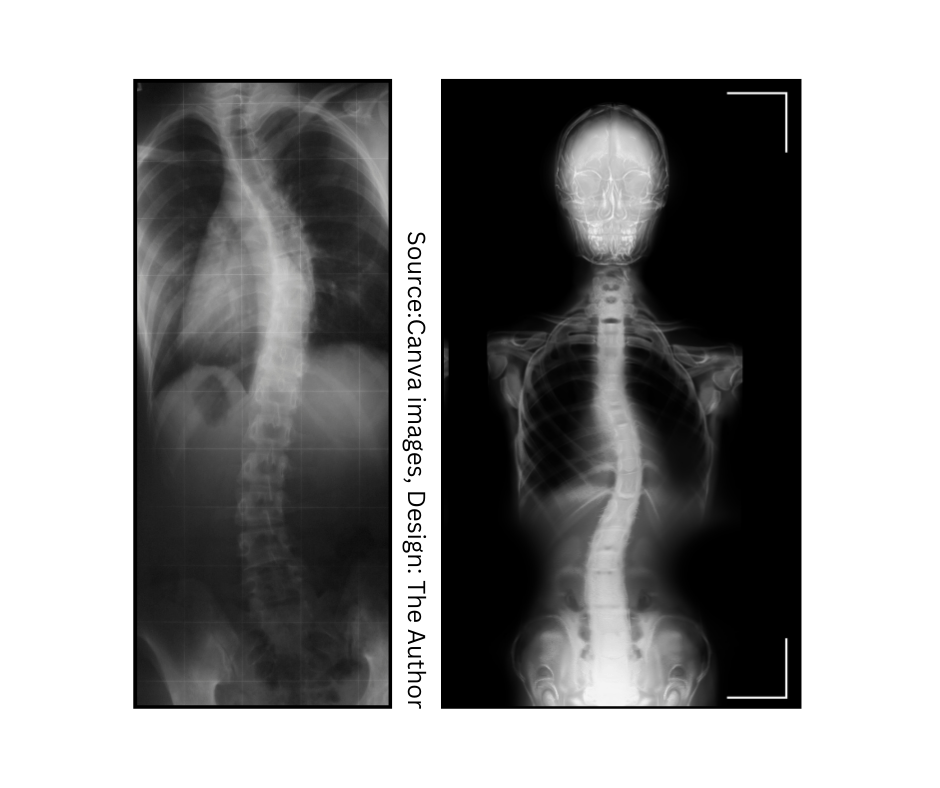

I explore scoliosis, chronic pain, disability, and inclusion through lived experience and neuroscience.

Living with scoliosis and chronic back pain can be incredibly challenging, both physically and mentally. No one with tell you what is 100% correct chronic pain management for you. Of course, medical personnel, chiropractic, or some experienced physiotherapist will do their best to help you, but it is your body, and you are experiencing pain and discomfort after all. Finding what works for you may take some time, and it is a process of comprehending how your body works, what is a chemical process, what you can influence, and how, and what you can not. It is a whole alchemy, and yes-it requires time and willingness to make significant improvements in the quality of your life.